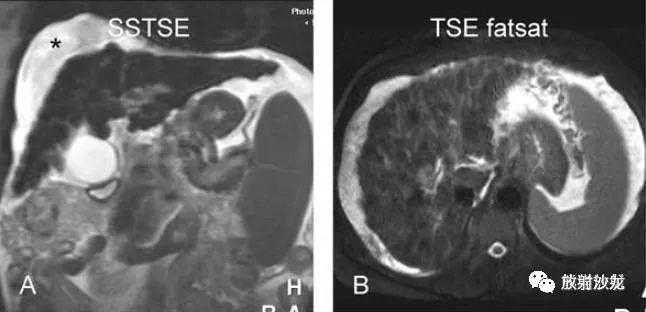

各基本序列信号特征

SSTSE:冠状T2WI,肝硬化,腹水,肝内多发低信号结节;

TSEfatsat:T2WI压脂,所有结节均呈低信号;

ART:动脉期,较大结节强化较明显,其余结节均不同程度有强化;

DEL:延迟期,大结节及其他结节均未见明显肿瘤包膜。

肝硬化,DN,MRI表现:

A~D:影像表现如上所述。